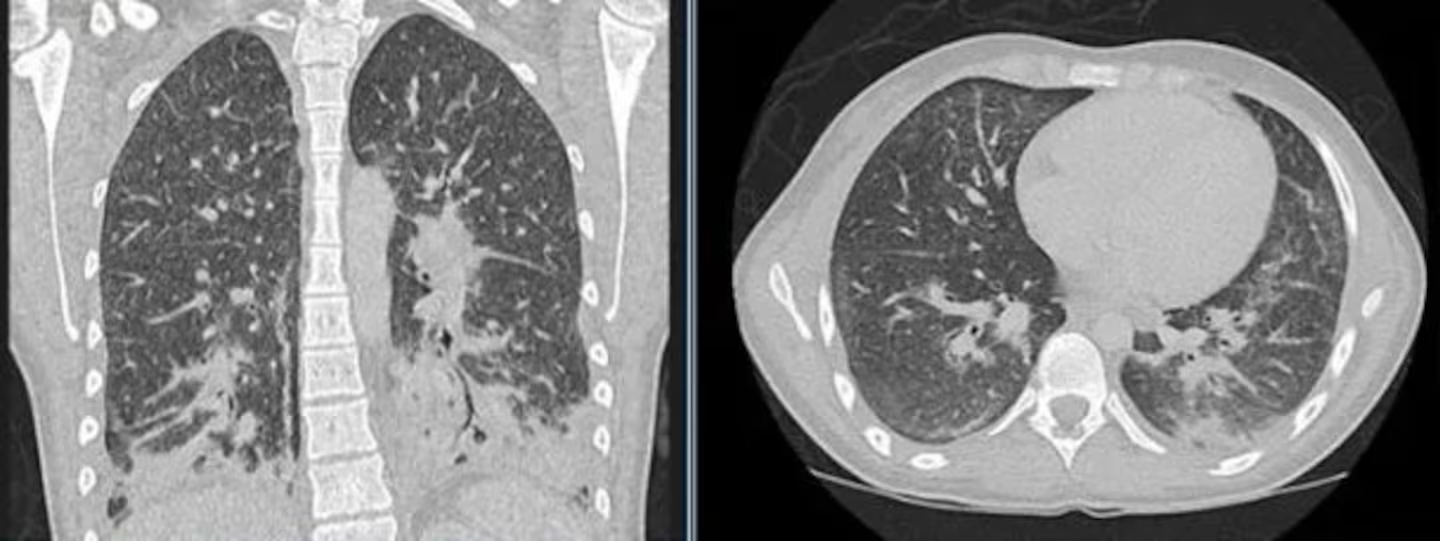

Una joven de Inglaterra tuvo que ser hospitalizada de urgencia tras una semana de intensa tos, escalofríos, fiebre alta y dificultad respiratoria. Al principio, los médicos creyeron que se trataba de neumonía bacteriana, pero al realizarle unas tomografías descubrieron que sus pulmones estaban llenos de “opacidades en vidrio esmerilado”, producto de haber usado el vaper de su novio durante un mes.

Normalmente, los pulmones sanos se ven negros en las radiografías y las tomografías computarizadas, pero en estas, gran parte se veía gris, lo cual indica que los sacos de aire de los pulmones podrían estar llenos de líquido u otras sustancias.

Frente a esto, le consultaron si era fumadora, a lo que ella respondió que hacía un mes estaba usando el vaper de su novio. Ahí fue cuando todo comenzó a tener sentido y, teniendo en cuenta los resultados de la radiografía, pudieron indicar que la joven presentaba EVALI, término utilizado para describir una enfermedad respiratoria aguda causada por los efectos tóxicos de los químicos utilizados al vaper.